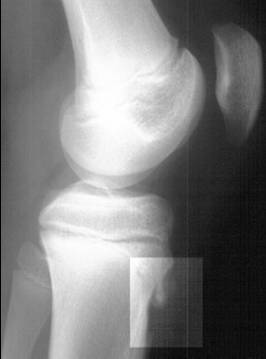

• Рентгенографическое исследование коленных суставов в боковых проекциях; часто наблюдаются характерные «хоботки» в области бугристости большеберцовых костей, нередко вводящие врачей в заблуждение; изолированные костные фрагменты небольших размеров, иногда в количестве 1-2-3. Картина представляется очень разнообразной, напоминающей дробления, искривления и надломы эпифизарного отростка.